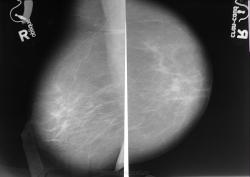

Пол пациента: Женский пол Тип патологии: Злокачественное новообразование Область исследования: Молочные железы Методы исследования: Rg https://radiomed.ru/sites/default/files/styles/case_slider_image/public/user/1787/dsc00463.jpg?itok=Qkb6l2z3 https://radiomed.ru/sites/default/files/styles/case_slider_image/public/user/1787/dsc00461.jpg?itok=VjRdWmJa ID:7637 Втр, 05/10/2010 - 17:29 #1 tatyana Не на сайте Был на сайте: 4 года 6 месяцев назад Зарегистрирован: 24.06.2009 - 08:33 Публикации: 2090 Да "самоуверенность дилетантов - предмет зависти профессионалов"